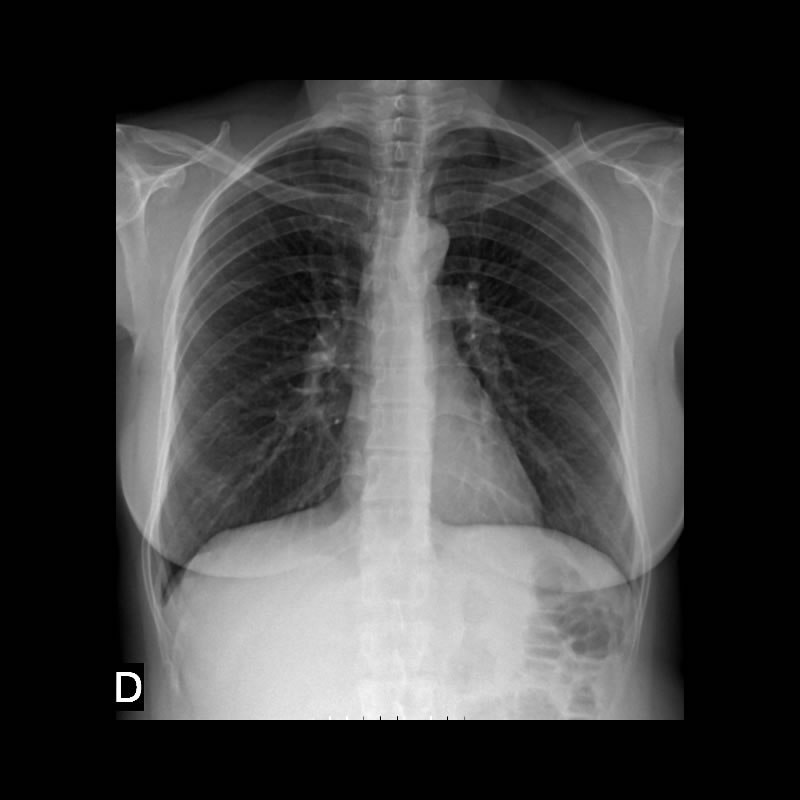

Mujer de 46 años con tos de larga data. Presenta como antecedentes: Enfermedad de Hashimoto medicada levotiroxina 88 mg/d

Dacrioadenitis bilateral hace 5 años

Ex tabaquista 20 cig/d durante 20 años

2 cesareas.